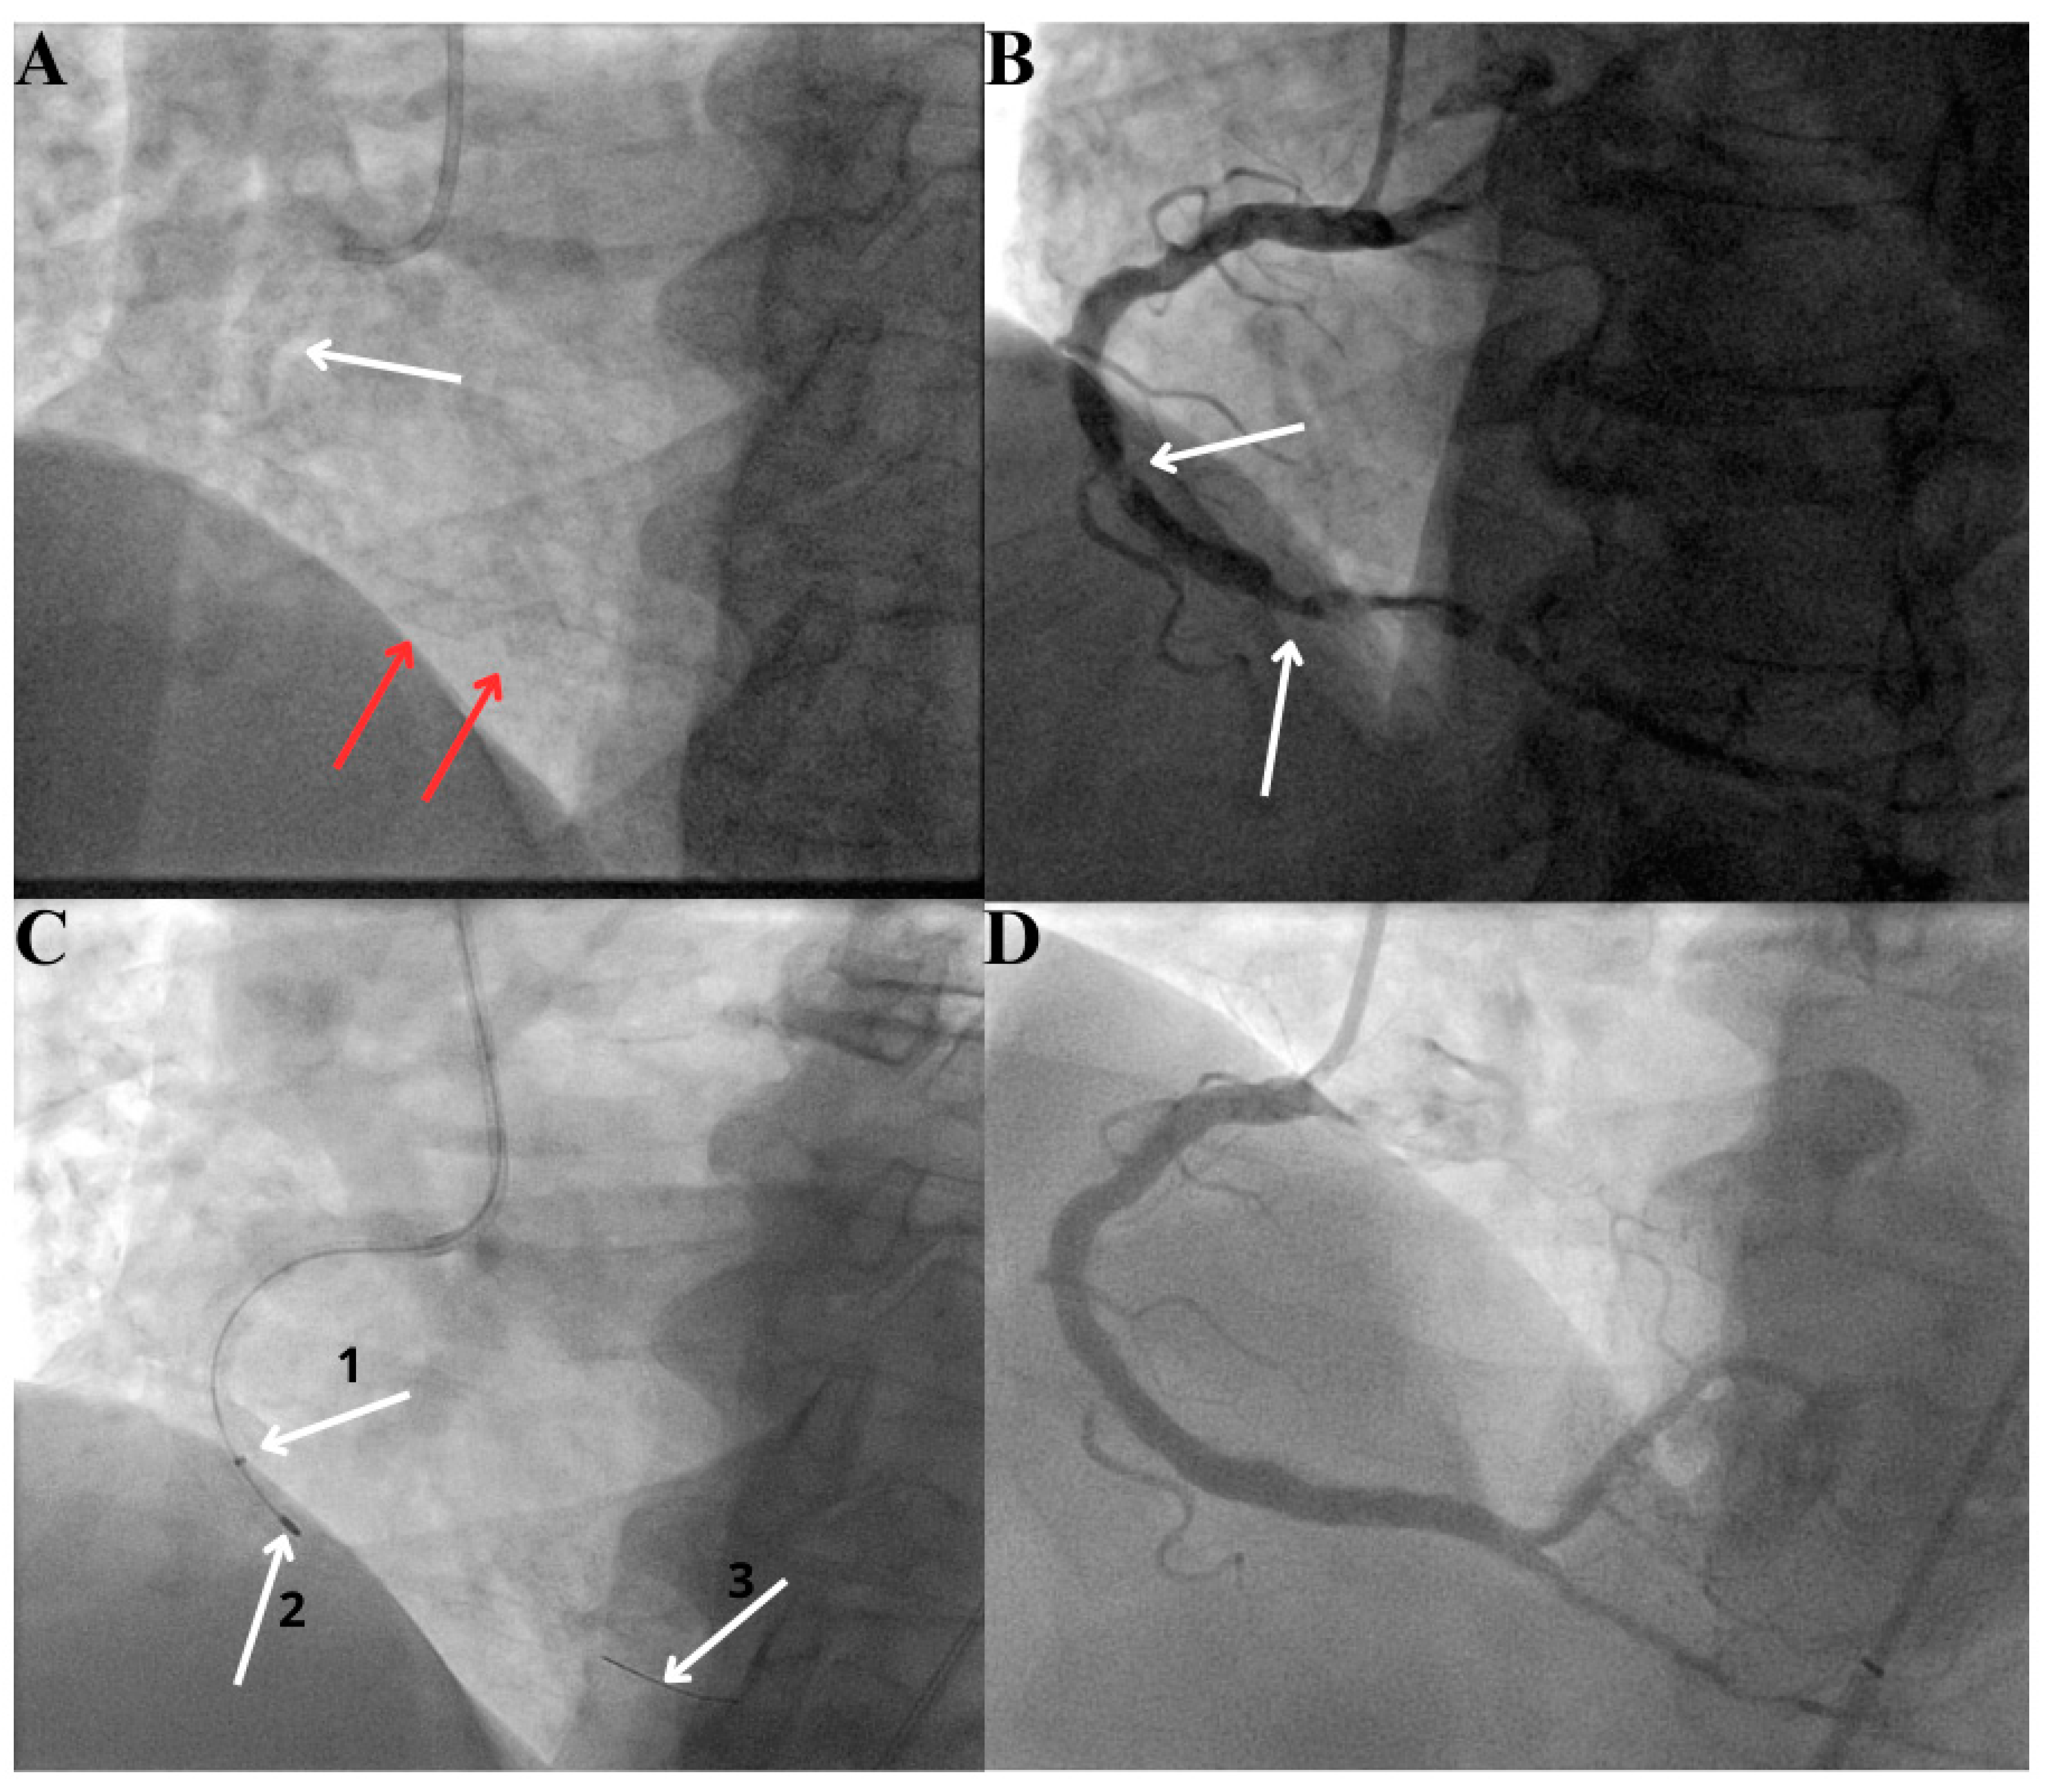

- Atherectomy techniques: rotational atherectomy (RA, rotablation) and orbital atherectomy (OA). The principle of these techniques is to ablate the calcific plaque while also creating plaque fractures and fissures.Rotational atherectomy was first described in 1987. It employs an olive-shaped burr with diamond chips embedded into it. The rotational atherectomy system consists of a console (which regulates the flow of air to the advancer, controlling burr rotation speed and also displays procedural parameters such as burr speed, duration of atherectomy, decelerations which are sudden drops in rotational speed), an advancer (which is used to control movement of the burr) and the burr itself which is introduced to the coronary vessel over a dedicated guidewire. The burr rotates at high speeds (140,000 to 180,000 rpm) and ablates the calcified tissue in a mechanism known as differential cutting (which preferentially ablates the inelastic tissue without damaging the vessel). The operator should use a pecking motion of the burr, which is a quick back and forth movement of the burr to the lesion and back. Decelerations in burr rotational speed should be avoided in order to prevent the burr stall which is serious complication (a situation in which the burr is stuck in the lesion and can no longer be moved or rotated). The particles of debris are <5 μm in diameter and can pass to the systemic circulation without causing distal embolization, however, some considerations are important to prevent the no-flow or slow-flow phenomenon (short burr runs, pauses between runs, appropriate rotational speed, avoidance of decelerations, appropriate pharmacotherapy, i.e., verapamil, nitrates, proper periprocedural anticoagulation). The burrs come in different sizes (from 1.25 mm up to 2.5 mm) to make it suitable for different vessel diameters (burr size should be <0.7 of a reference vessel diameter). PREPARE-CALC (patients were randomized to a lesion modification with use of either RA or cutting/scoring balloons) and ROTAXUS (randomization to groups with RA followed by stenting or stenting without RA) trials indicated that RA before stent implantation is feasible and effective nearly in all patients with heavily calcified lesions [39,40]. A schematic representation of the RA burr is shown in Figure 3.Orbital atherectomy uses two physical mechanisms: differential sanding and centrifugal forces. The crown rotates eccentrically (off-center), creating an “orbital” motion as it spins around the catheter shaft. Compared to RA, there is only one size of the crown, but use of different speed settings makes it suitable for different vessel sizes (the range of the orbital motion is higher with higher speeds). Two speed settings are available; low speed (80,000 rpm) is often used for the first pass, while the higher speed (120,000 rpm) can be utilized in certain lesions, especially in vessels with a larger diameter. Contrary to RA, OA works bidirectionally both when it is advanced and retracted. The ORBIT II trial has proved the safety of the procedure by indicating a low rate of adverse ischemic events [41]. A large, randomized ECLIPSE trial (OA vessel preparation compared with high-pressure balloons angioplasty and/or cutting balloons) is ongoing [42].